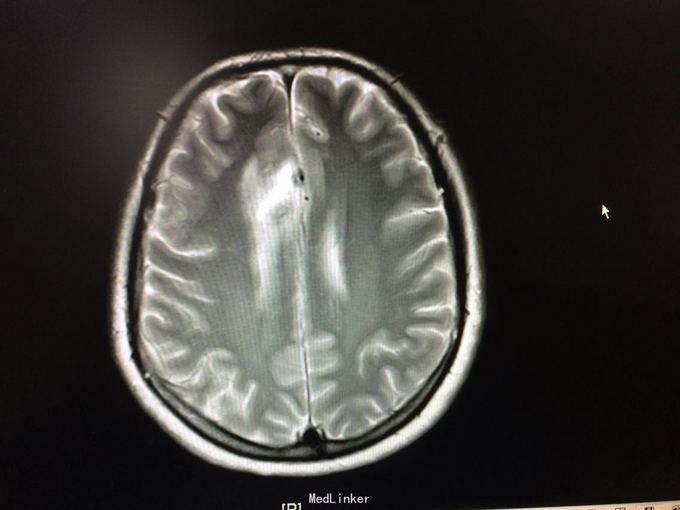

主诉:记忆力减退3月,左侧肢体乏力3天 病史:患者51岁女性,3月前无明显诱因出现记忆力减退,伴头痛,3天前出现站立不稳,左侧肢体乏力,步行困难,当地CT提示右侧额叶低密度灶,

查体:左侧上肢肌力4级,右侧5级,轻瘫试验左侧阳性 辅助检查:右侧额叶、胼胝体膝部病变伴出血,增强扫描明显强化。考虑胶质瘤

诊断:右侧额叶多发脑软化灶 处理:全麻下行右侧额叶占位病变切除术,术后病理提示:符合脑软化,未见明显肿瘤因素等